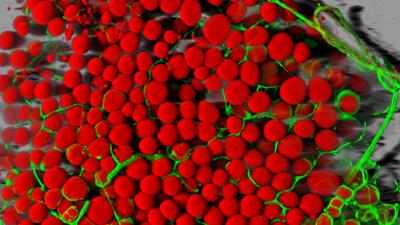

In laboratory experiments, UCSF researchers successfully beat back the growth of aggressive liver cancers using a surprising new approach.